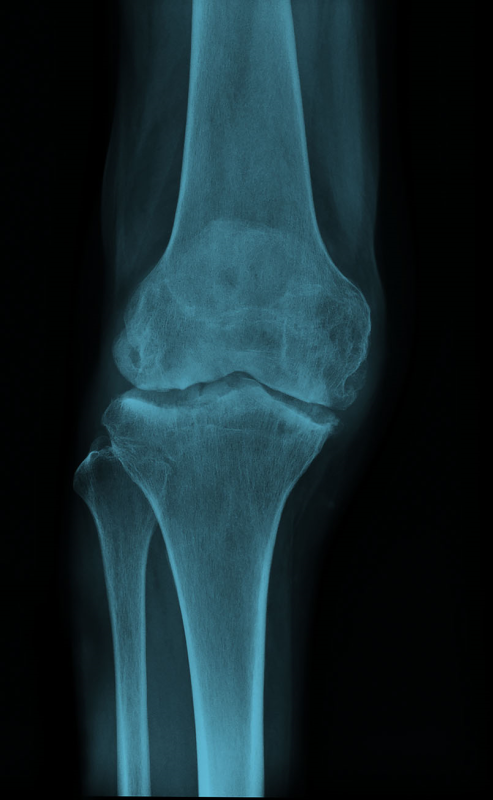

РОЗПІЗНАЙТЕ НА РЕНТГЕНОГРАМІ СУГЛОБ, ЩО СКЛАДАЄТЬСЯ З ТРЬОХ СУГЛОБІВ, ЯКІ МАЮТЬ СПІЛЬНУ КАПСУЛУ.

варіанти відповідей

СУГЛОБ СКЛАДНИЙ. УТВОРЕНИЙ СУГЛОБОВИМИ ПОВЕРХНЯМИ МЕДІАЛЬНОГО І ЛАТЕРАЛЬНОГО ВИРОСТКІВ, ЯКІ Є В ОБОХ КІСТКАХ, ЩО ЙОГО УТВОРЮЮТЬ. РОЗПІЗНАЙТЕ СУГЛОБ.

КОЛІННИЙ С.

ЛІКТЬОВИЙ С.

ГОМІЛКОВО--СТОПНИЙ С.

ПРОМЕНЕВО-ЗАП'ЯСТКОВИЙ С.